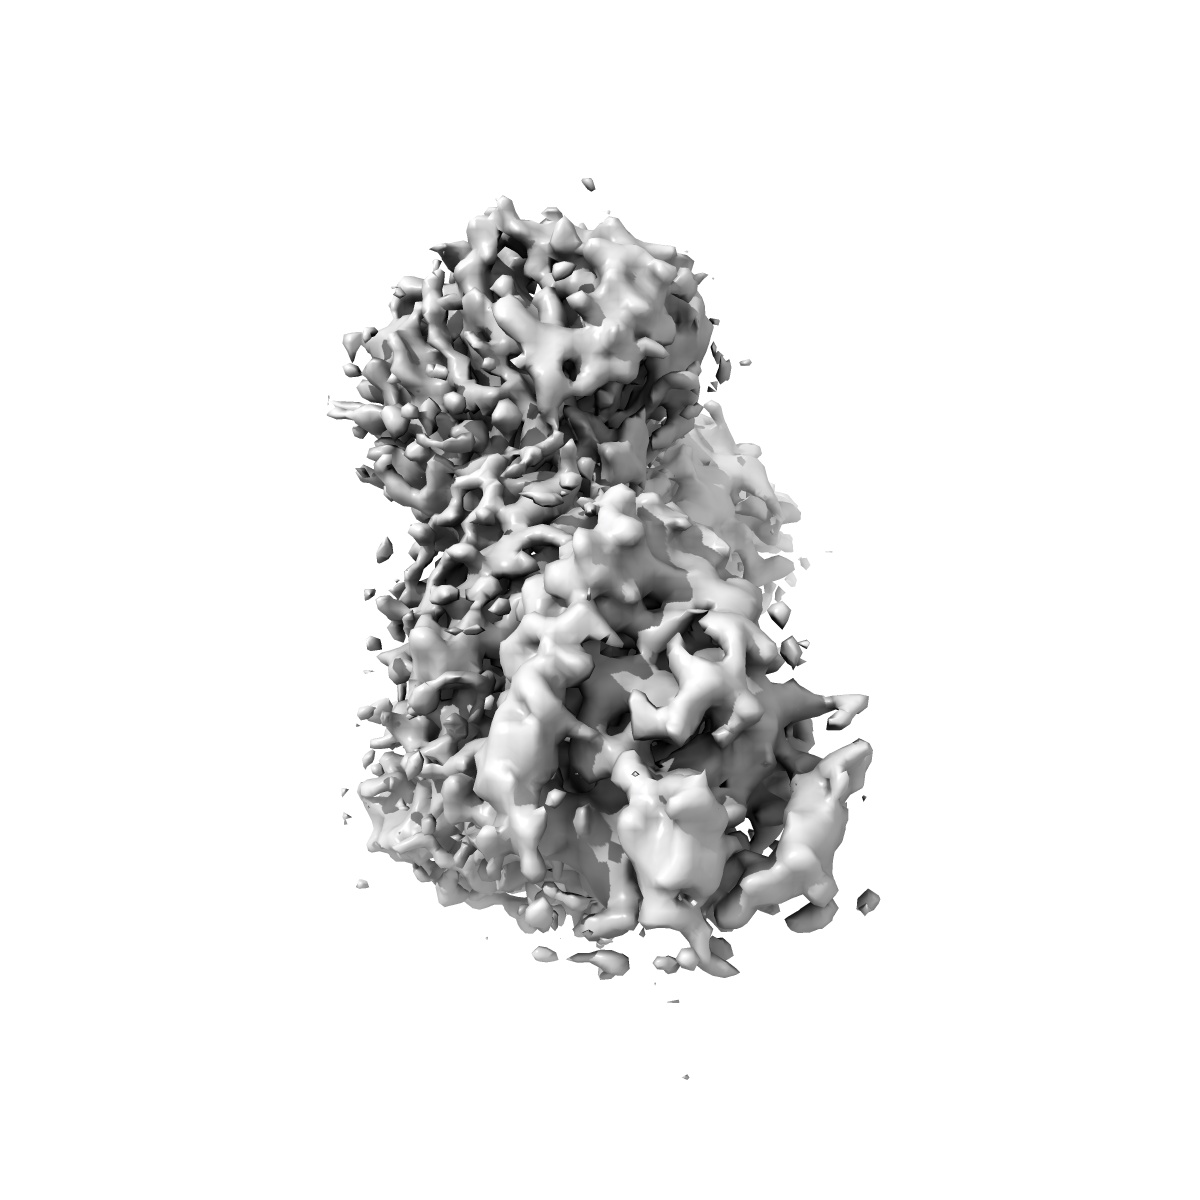

CryoEM structure of non-neutralizing bivalent antibody CBH-4B in complex with Hepatitis C virus envelope glycoprotein E2

Cryo-EM structures of HCV E2 glycoprotein bound to neutralizing and non-neutralizing antibodies determined using bivalent Fabs as fiducial markers.